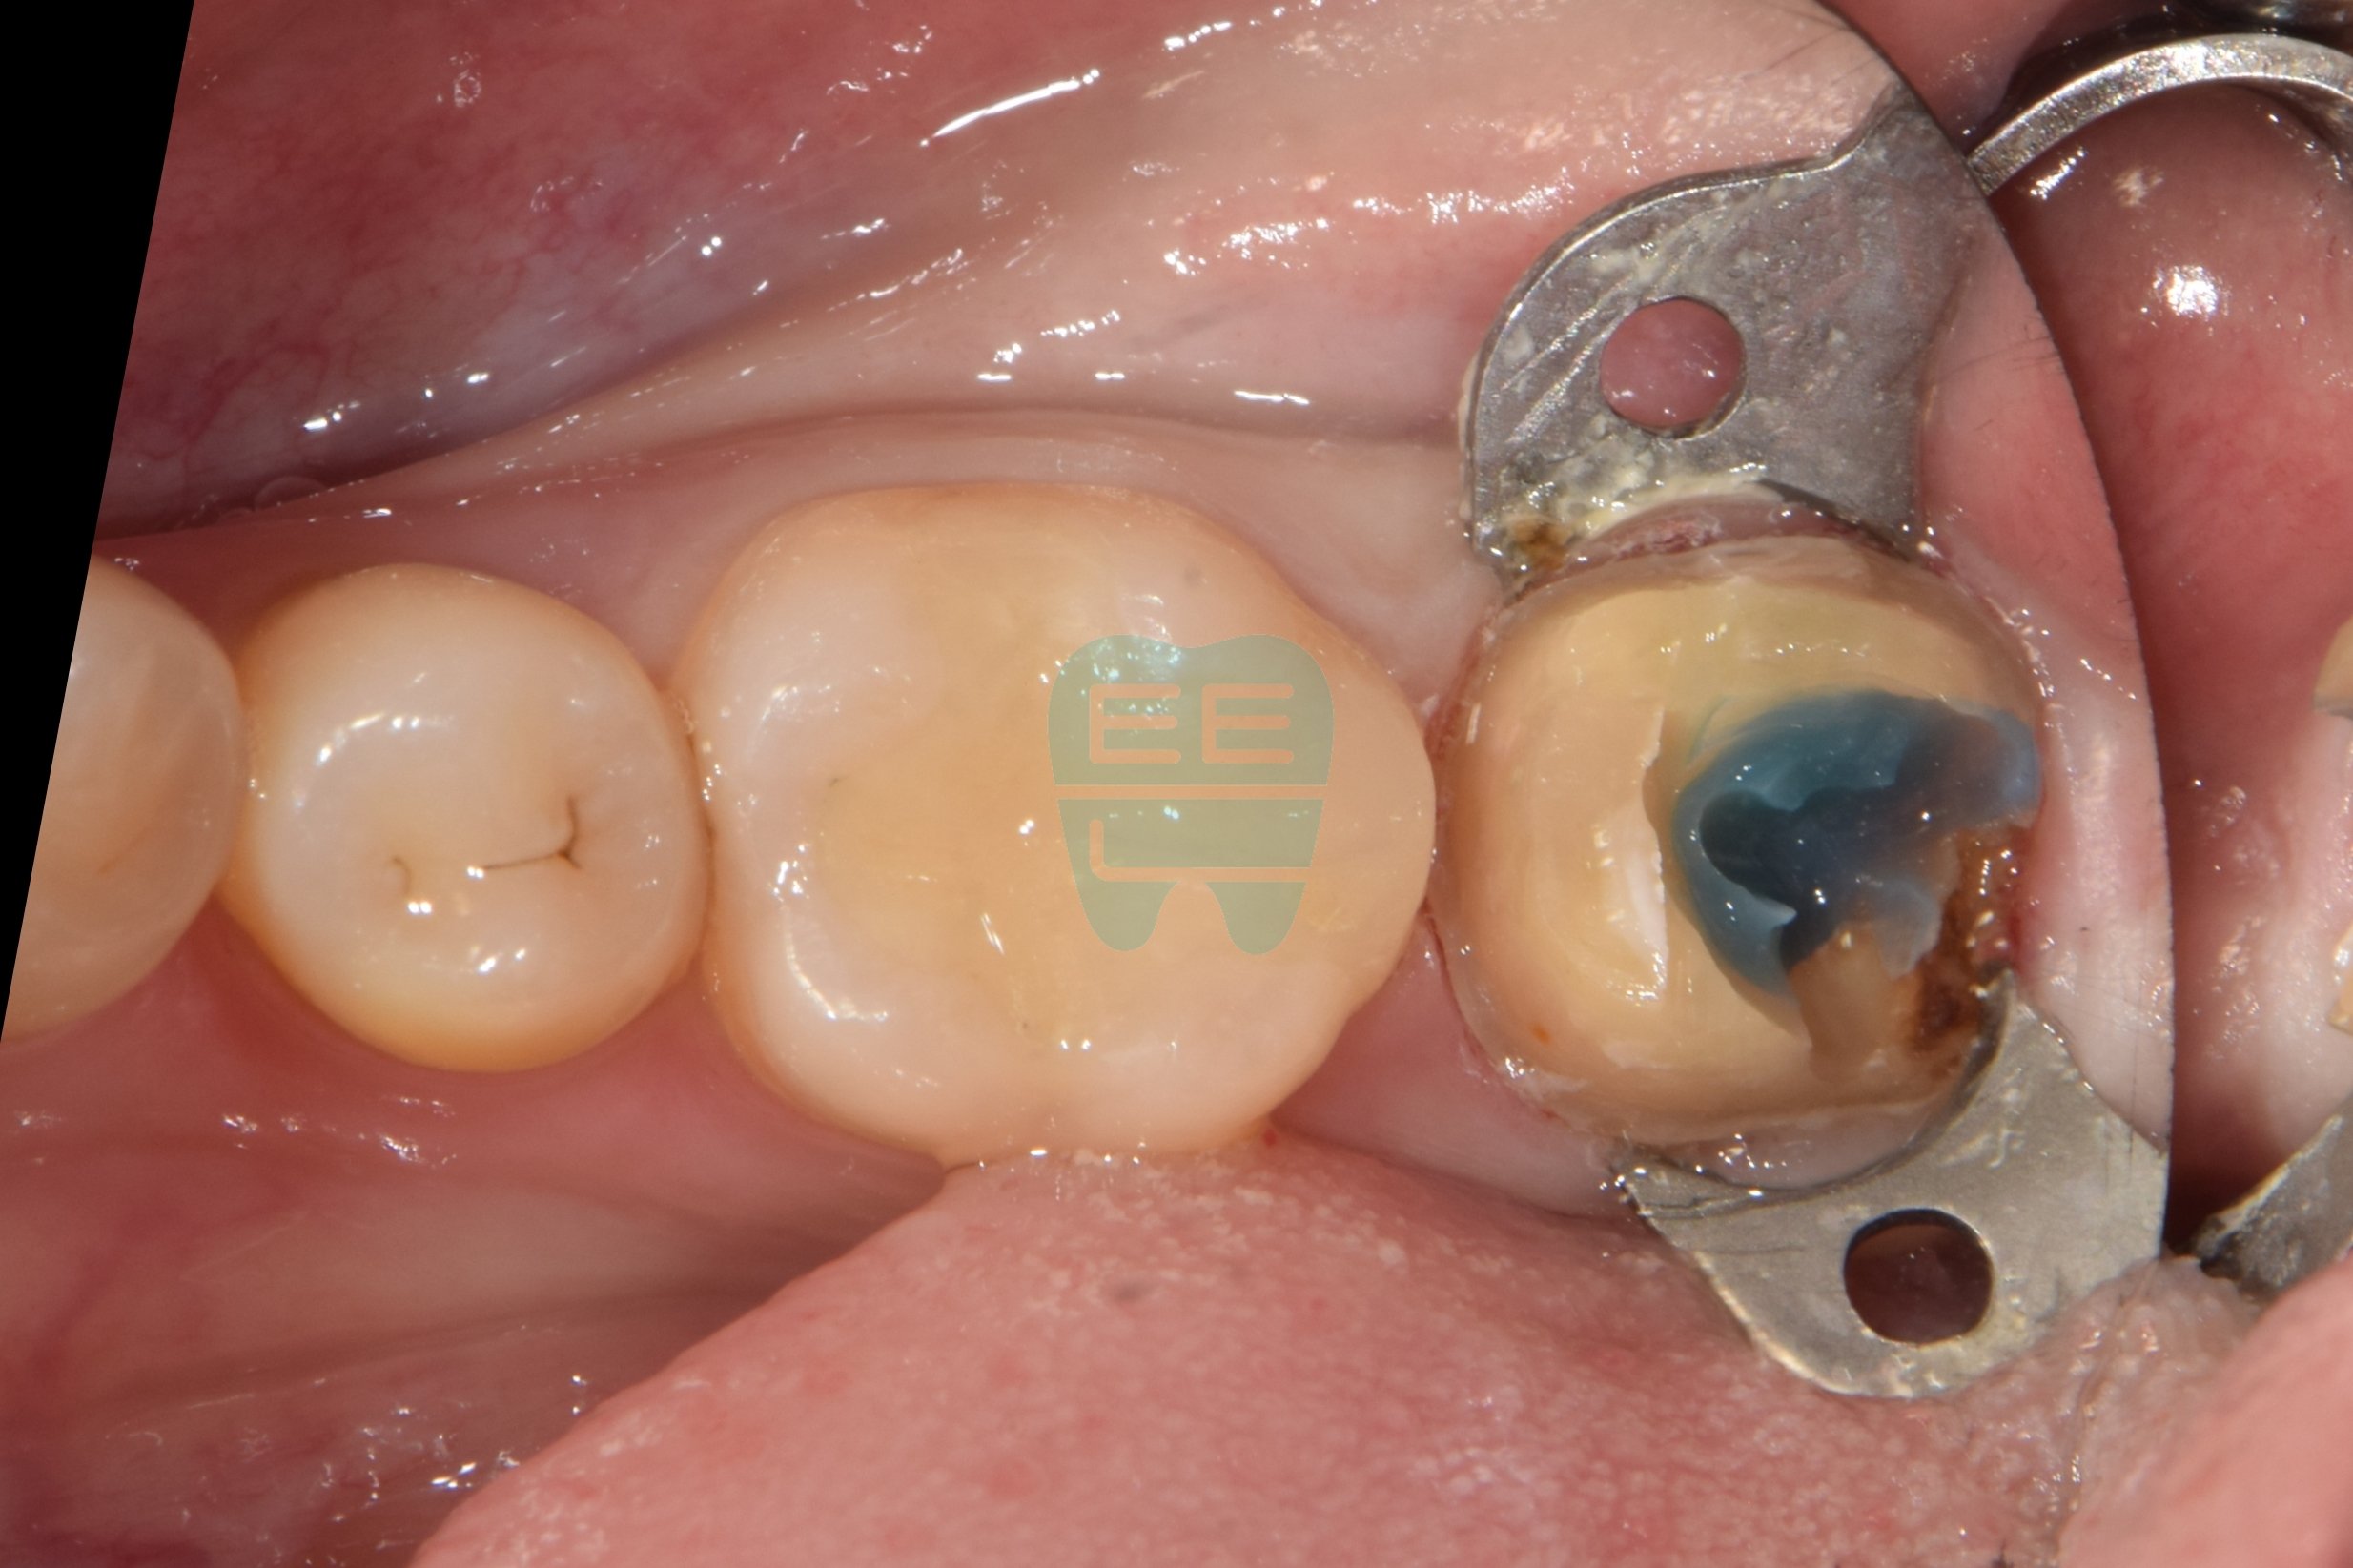

크라운 하방 2차우식 치료를 위한 레진코어 빌드업 방법

초진상태로 찝찝한 냄새가 나신다 하심크라운 제거후 상태로 파란색 코어가 관찰됨코어 제거후 상태로 원심 2차우식으로인한 leakage로인한 악취로 진단함충치와 레진코어를 모두 제거한 상태러버댐과 원심 격리를 위한 매트릭스 밴드를 장착중인 모습러버댐 하에 원심 레진wall을 형성한 모습

사진 3